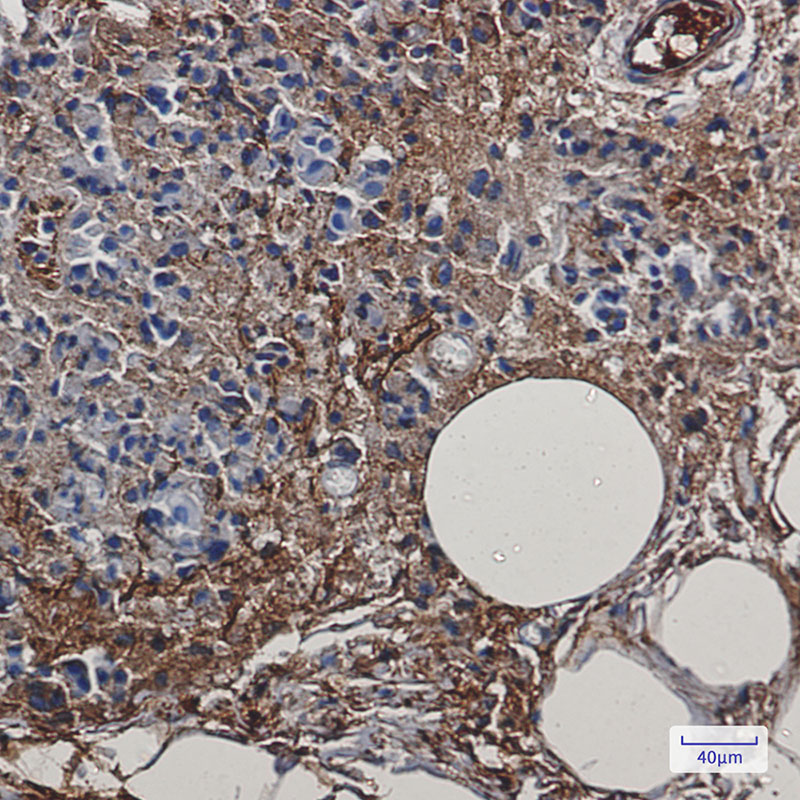

Immunohistochemistry analysis of paraffin-embedded Human breast cancer using Creatine kinase B type antibody. High-pressure and temperature Sodium Citrate pH 6.0 was used for antigen retrieval. |